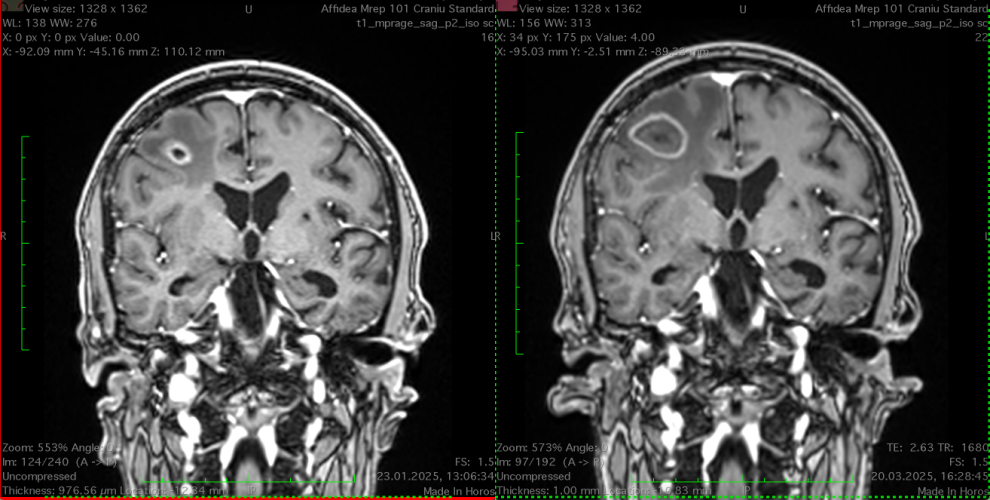

- Imagistică cerebrală: RMN-ul cu substanță de contrast este metoda de elecție, dar și CT-ul poate fi util.

Tratamentul metastazelor cerebrale este complex și personalizat în funcție de: numărul de metastaze, localizare, dimensiune, starea generală a pacientului, tipul tumorii primare și alte comorbidități.

- Scopul operației este reducerea încărcării tumorale, obținerea unui diagnostic histopatologic (când nu există deja) și ameliorarea simptomelor prin reducerea edemului cerebral, a efectului de masă și a hipertensiunii intracraniene.

Fără tratament, supraviețuirea este de ordinul săptămânilor. Cu tratament, unii pacienți pot trăi luni sau chiar ani, mai ales în cazul unui control bun al bolii sistemice și a metastazelor cerebrale puține. De exemplu, pacienții cu metastază cerebrală unică operată și iradiată pot avea o supraviețuire de peste 1-2 ani. De multe ori, după un tratament corect și complet al metastazelor cerebrale (operație și/sau radioterapie), evoluția pacientului va fi dată de progresia leziunii primare, nu de cea a determinărilor secundare.